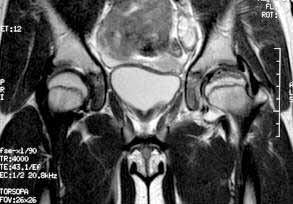

The eleven year old female gymnast presents with an xray image of the left hip which looks more benign than the MRI which shows coxa plana with resorption of bone in a large area of the femoral capital epiphysis and widening of the femoral neck. These changes and the patient's gender and age mean a poor prognosis for Legg-Perthes disease which I believe this case represents. Was the MRI done somewhat later in the course of time than the X-rays? I could not make out dates on the images. There is one feature of the MRI which might be favorable: the enlarging femoral head does not seem to extrude far beyond the edge of the acetabulum as marked by the thorn sign. This indicates that satisfactory containment might still be obtained by upper femoral varus-producing osteotomy. I would confirm this possiblity by a dynamic arthrogram at the time of surgery; if the femoral head centers well enough with up to 30 degrees abduction for the edge of the acetabulum to drop down around it, the upper femoral osteotomy might bring a good short term outcome. Otherwise, I might consider a double osteomy: upper femoral and innominate. Left alone, the hip will probably go on to hinge-abduction with attendant pain and stiffness.

Regarding this case, I am grateful by your opinion. After careful analysis of the history and films, I am convinced that this is not a Perthes disease. In fact, on this case there are a violent traumatic event that have provoked the lesion, which is not compatible with Perthes. On the other hand, the MRI pattern is not what I am used to seeing. The patient presents a voluminous joint effusion and a image of anterior impaction of the femoral head with a thin layer of subchondral necrosis under the compacted zone (jb02).

In Perthes, the necrosed zone generally includes a deep thickness of the epiphysis. On the other hand, it doesn't seem to have articular cartilage thickening, one of the 1st signs of Perthes. Finally on the MRI one can see a rupture of the lateral rotator muscles, including gemelli, obturators and quadratus, with abundant extra-articular effusion, which never happens in Perthes disease and shows the violence of the accident (jb01).